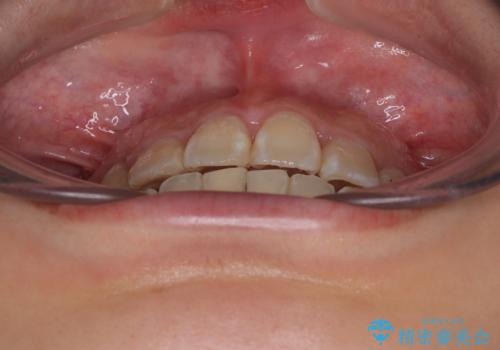

- 上下前歯のデコボコを気にして来院された患者様です。

上顎は両側の犬歯が骨内に埋伏しており、乳歯が残存している状態でした。

歯肉内に埋もれている場合には牽引することも可能ですが、両歯ともに骨内に完全に埋もれていたため、牽引することは不可能と判断しました。

口元の突出感があるわけではなく、叢生の程度もシビアではありませんでしたが、顎骨が小さく、左右ともに最後臼歯が歯肉に埋もれているため、下顎は左右第二小臼歯を抜歯することとしました。

上顎は左右ともに残存している乳歯を抜歯し、上下歯列を整えることとしました。